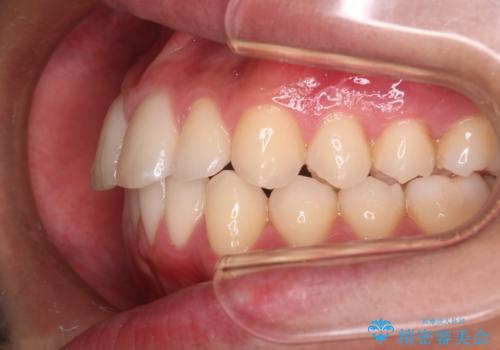

【インビザラインモニター】前歯が出ているのが気になる

- 上の前歯が出ているのが少し気になるとの事で来院されました。

インビザライン希望のため、IPR(歯と歯の間を削る処置)を行うことで、前歯の位置とがたつき整える治療計画を立てました。

患者様よりシュミレーション通りに歯が動くか心配との事だったので

出来るだけ計画通りに歯を動かすために、マウスピース1枚あたりの使用時間を長めに使っていただきました。

そのため、多少治療期間が延びましたが、リファイメント(マウスピースの再発注)なしで終了することができました。